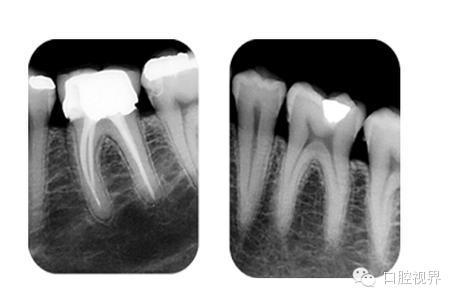

(这是从网上找的一份资料,不同的投射角度拍出的影响对比)